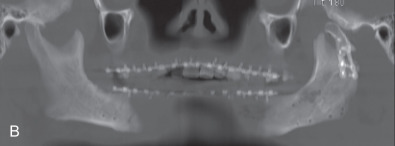

All of these systems allowed for convalescent function – life without MMF. RIF had the potential of dramatically shortening the course of treatment. However, its use was highly technique-sensitive with a steep learning curve. Thus, the incidence of complications increased dramatically due to operator error. Complications related to inadequate reduction – “the OIF” (open internal fixation … without the reduction) ( Figs. 1.16.1–1.16.3 ), inadequate fixation ( Figs. 1.16.4–1.16.7 ) and surgical misadventure ( Fig. 1.16.8 ) began to appear. Indeed, by the early 1990s operator error was the number one cause of mandibular fracture complications. Quite obviously, RIF is very unforgiving. When done poorly, one has a rigidly fixed mistake. The latest series of misadventures are related to the use of IMF screws. Bone-anchored arch bars will most likely be next. Not all believe that RIF and convalescent function is cost-effective with respect to the increased cost, potential for complications, and patient acceptance.